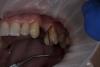

carloss Опубликовано 29 сентября, 2013 Поделиться Опубликовано 29 сентября, 2013 Ампутировать то можно, но места всё равно, мне кажется, маловато для двух имплатов.. с другой, наверное, после удаления синус-лифтинг не избежен.. думайте сами)) я бы ампутировал, потом пружиной задвинул бы верхние моляры немного дистально.. как на картинке, только наоборот.. http://savepic.su/3345395.jpg Но у вас же нет таких пружин)).. поэтому, думаю если поставите миниипланты дистально, то удастся и немного дистализировать и сделать интрузию.. потом, в зависимости от карманов, расстояний и т д, решать - ампутировать или нет.. Ссылка на комментарий

Art 7 Опубликовано 29 сентября, 2013 Автор Поделиться Опубликовано 29 сентября, 2013 carloss в Вашем случае есть куда толкать, в моём 3 моляра в плотном контакте)) Ссылка на комментарий

carloss Опубликовано 29 сентября, 2013 Поделиться Опубликовано 29 сентября, 2013 Третий там явно лишний)).. Хотя я и три толкал таким образом.. Тем более, что они раньше там уже были)).. Это не совсем шутка)) Ссылка на комментарий